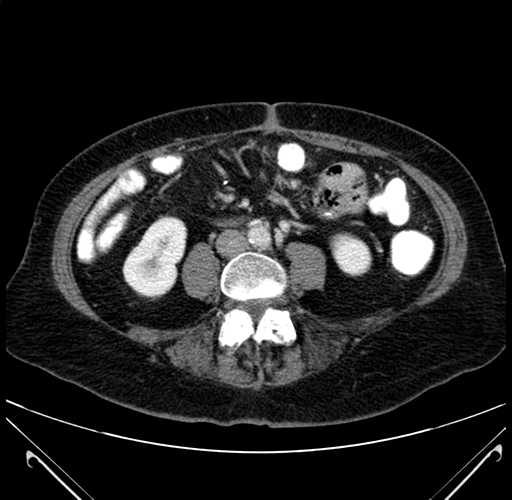

Pre-Chemo: Coronal Venous

Coronal Venous